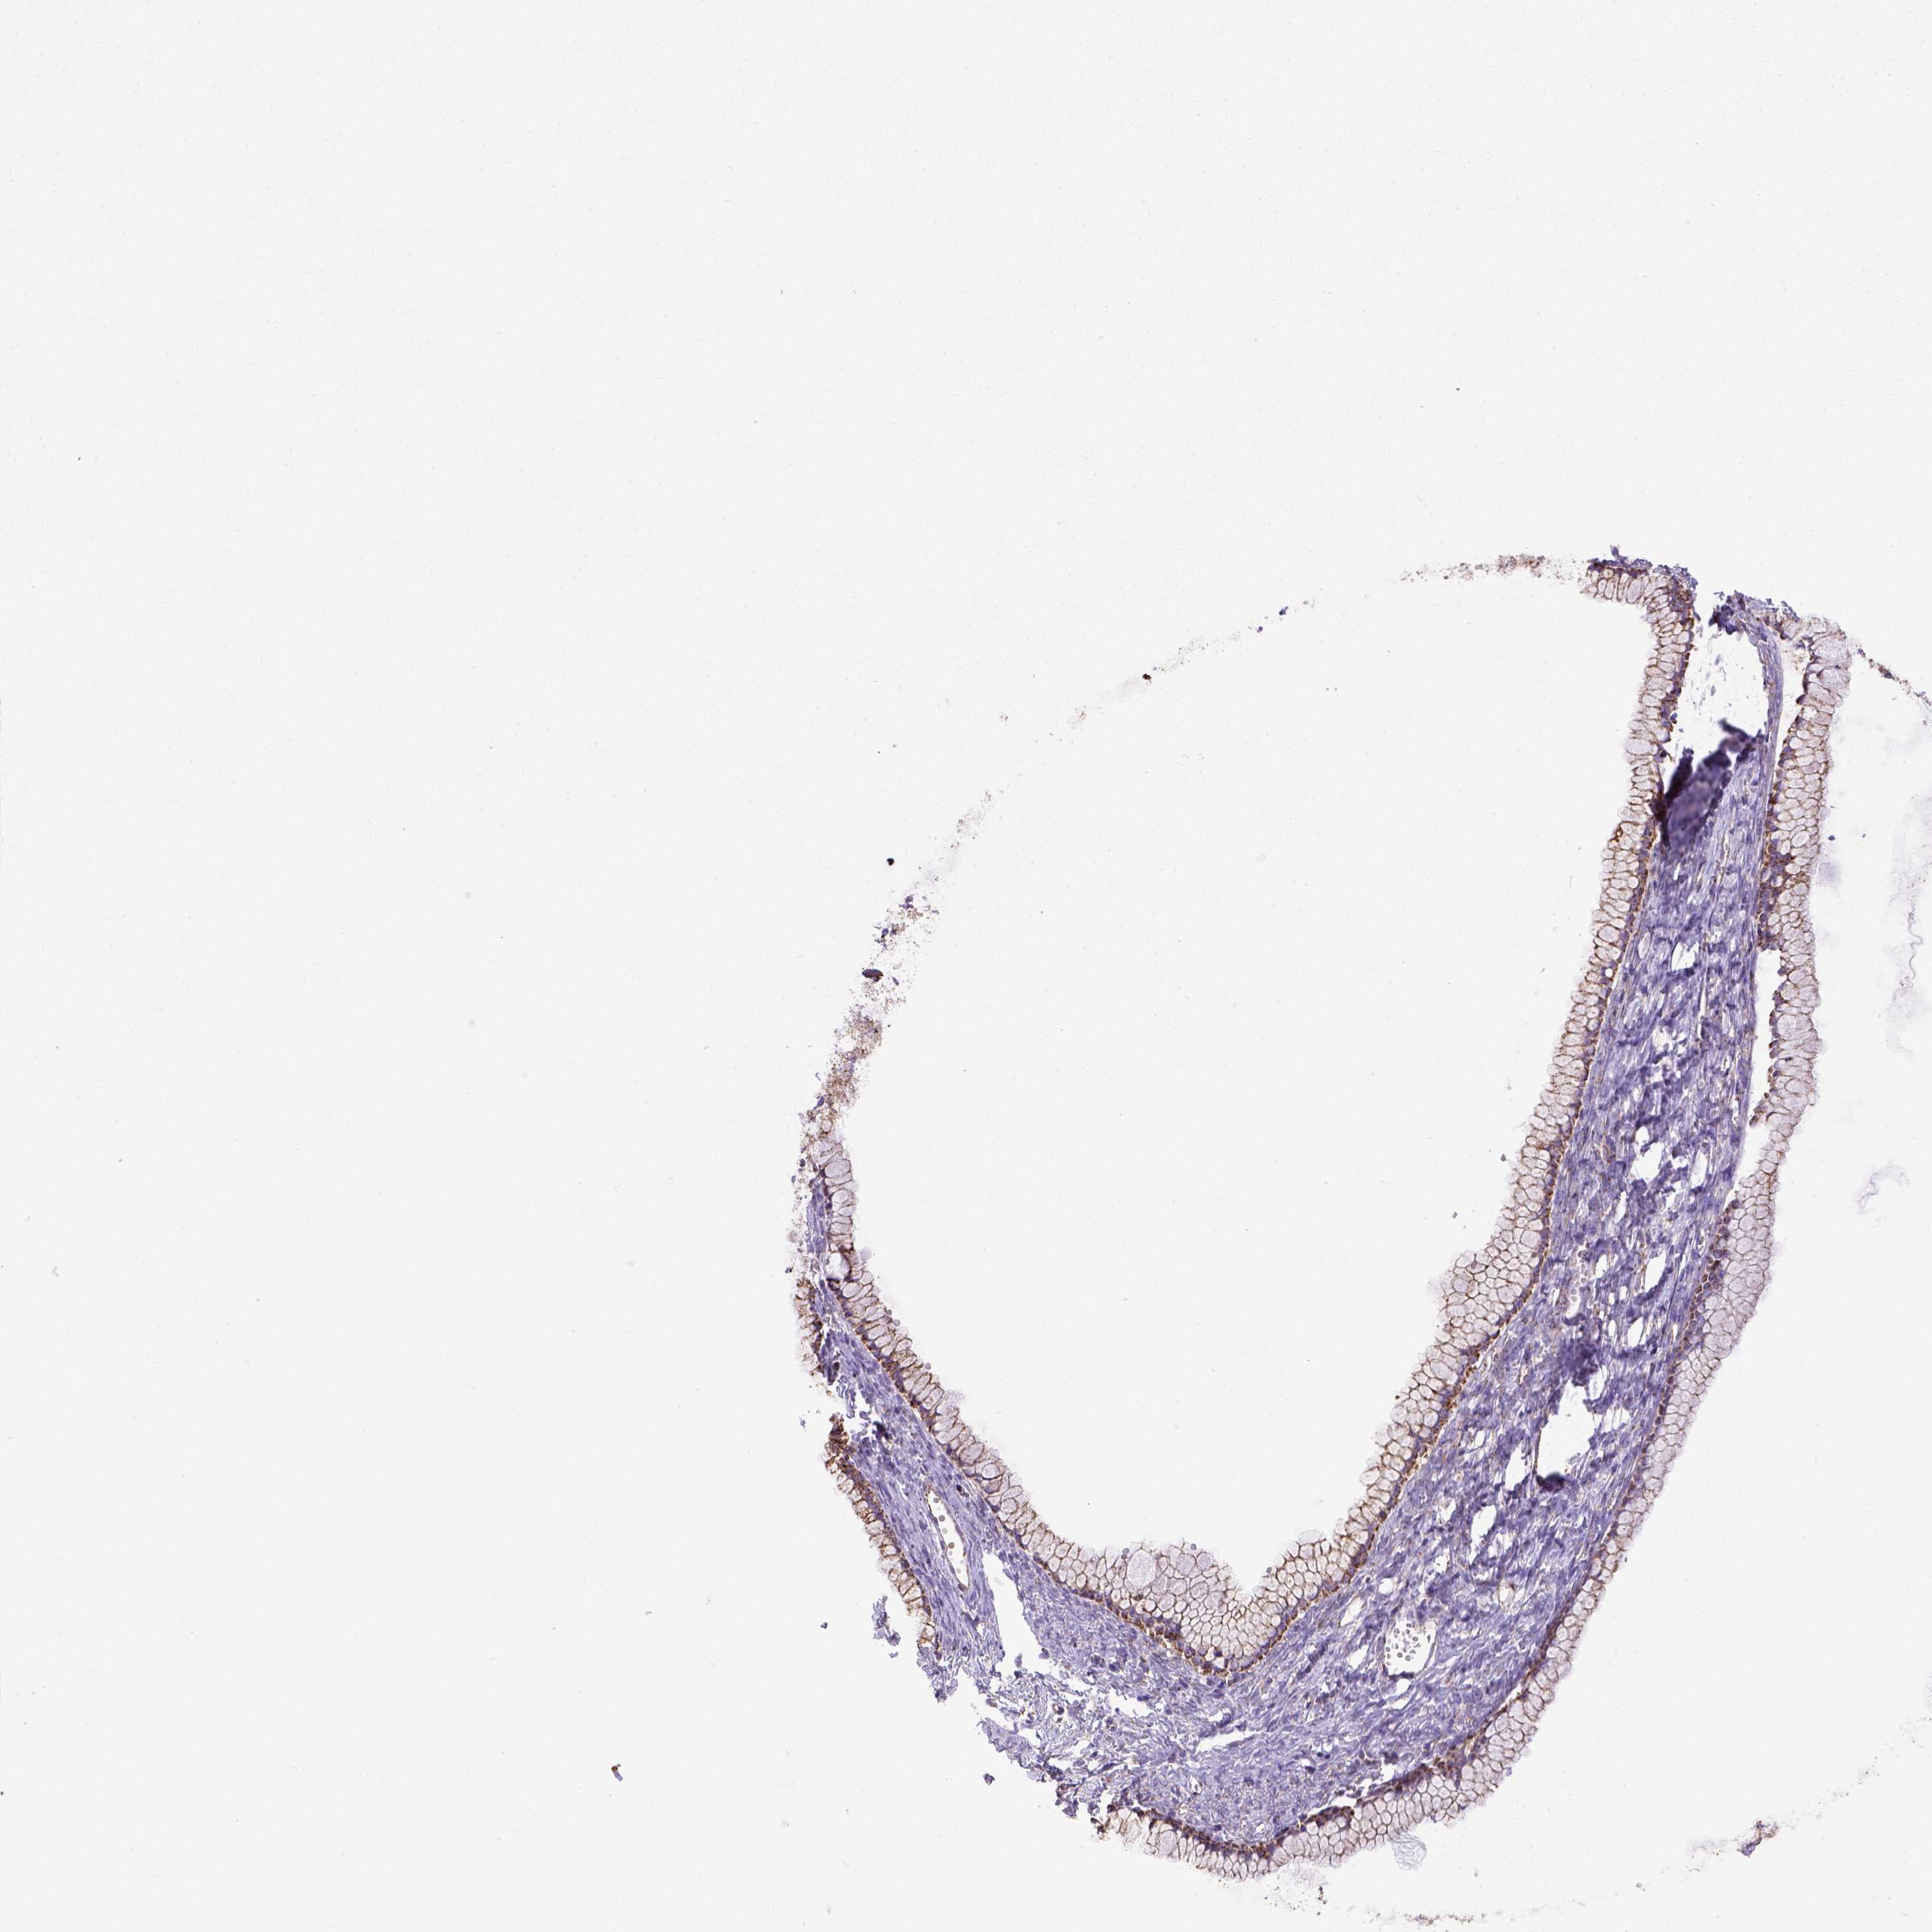

OVARIAN CANCER - Protein expressioni

A mouse-over function shows sample information and annotation data. Click on an image to view it in a full screen mode. Samples can be filtered based on level of antibody staining by selecting one or several of the following categories: high, medium, low and not detected. The assay and annotation is described here.

Note that samples used for immunohistochemistry by the Human Protein Atlas do not correspond to samples in the TCGA dataset.

Antibody stainingi

Antibody staining in the annotated cell types in the current human tissue is reported as not detected, low, medium, or high, based on conventional immunohistochemistry profiling in selected tissues. This score is based on the combination of the staining intensity and fraction of stained cells.

Each image is clickable and will lead to virtual microscopy that enables deeper exploration of all samples and also displays staining intensity scores, fraction scores and subcellular localization as well as patient and tissue information for each sample.

Antibody HPA069328

Antibody CAB016241

Cystadenocarcinoma, serous, NOS

Cystadenocarcinoma, mucinous, NOS

Carcinoma, endometroid